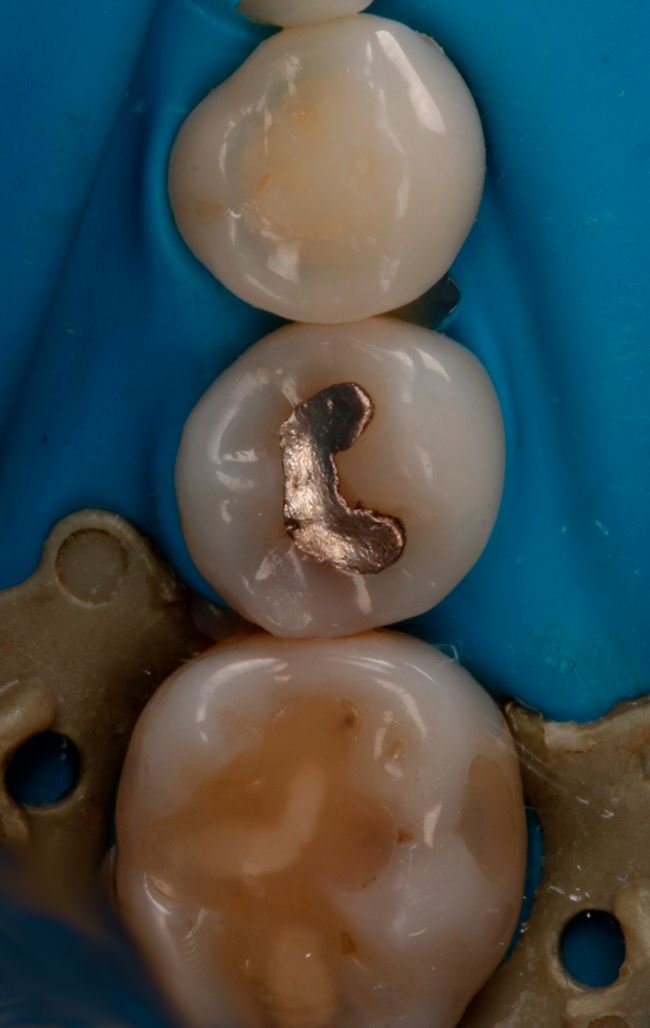

W przypadku zęba 45 wyraźnie widać, że DIAGNOcam się sprawdził, gorzej ze zdjęciem skrzydłowo-zgryzowym. Teraz pozostało już tylko założenie formówki (ryc. 11), wypełnienie ubytku, w tym przypadku nanohybrydowym materiałem kompozytowym Harmonize (Kerr) (ryc. 12 i 13), dostosowanie wypełnienia i wypolerowanie (ryc. 14). Chociaż to jeszcze nie wszystko. Ostatnią czynnością powinno być zmotywowanie pacjentki do codziennego stosowania nici dentystycznej. Obrazy z DIAGNOcamu świetnie się do tego nadają.

Ryc. 12. Ząb 45 po założeniu formówki jednościennej i klina.

Ryc. 13. Odtworzenie ściany stycznej w zębie 45 nanohybrydowym materiałem kompozytowym Harmonize Enamel A3.